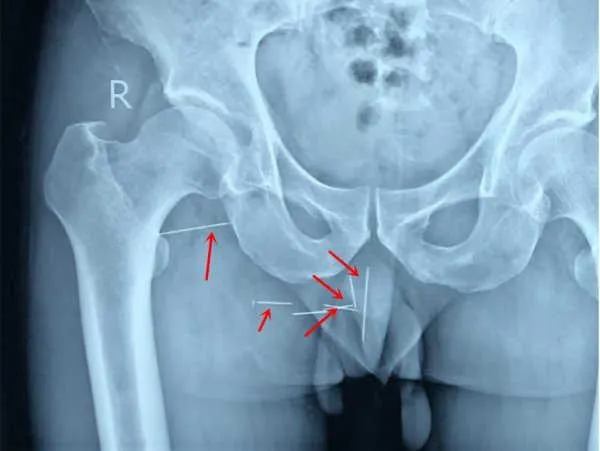

Phim chụp X-quang cho thấy nhiều cây kim nằm ở vị trí mông của người đàn ông. Ảnh: ODD

Phim chụp X-quang cho thấy có tám cây kim nhọn đang cắm sâu vào mông của ông ta. Ban đầu Chen cũng không nhớ vì sao nó lại ở đó. Tuy nhiên, sau đó ông nhớ lại có một mình từng bị té vào một đống rác chỗ làm việc. Ban đầu Cheng chỉ nghĩ rằng bị một vài cây cắm vào lưng và ông sau đó cũng đã loại bỏ chúng. Rất tiếc là ông đã không lấy nó ra hết.